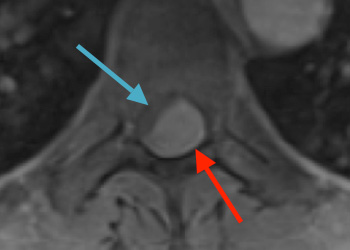

Spine:

Central Cord Syndrome

Author: Yusef Imani M.D., F.A.A.N.S., Read More!